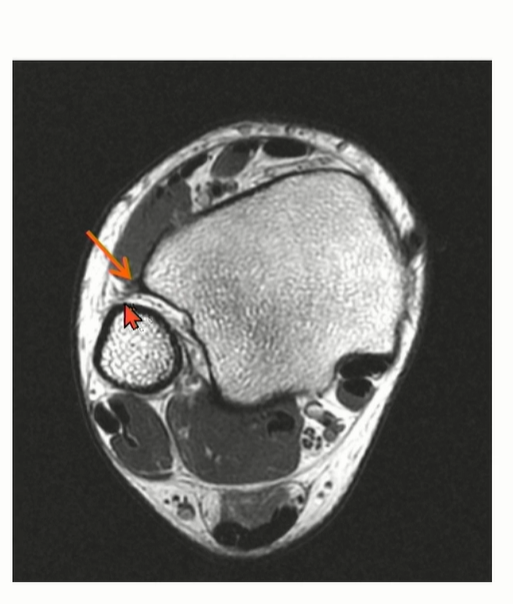

Peroneal tendon을 landmark로 이용해서 CFL를 찾는 것도 연습해야 함.

Axial cut과 coronal cut에서 모두 확인할 수 있는데, Axial cut의 경우에는 peroneal tendon 내부에 위치한 것을 확인할 수 있다.

MRI에서는 coronal cut에서 AITFL 를 관찰하기 용이하다. Multi-fascicular 구조이기 떄문에, Tear로 오인하면 안됨.

특히 Axial cut에서는 일부 cut에서 discontinuity 가 관찰될 수 있는데, oblique한 주행 방향으로 인한 정상 소견일 수 있다는 것을 염두해야 한다.